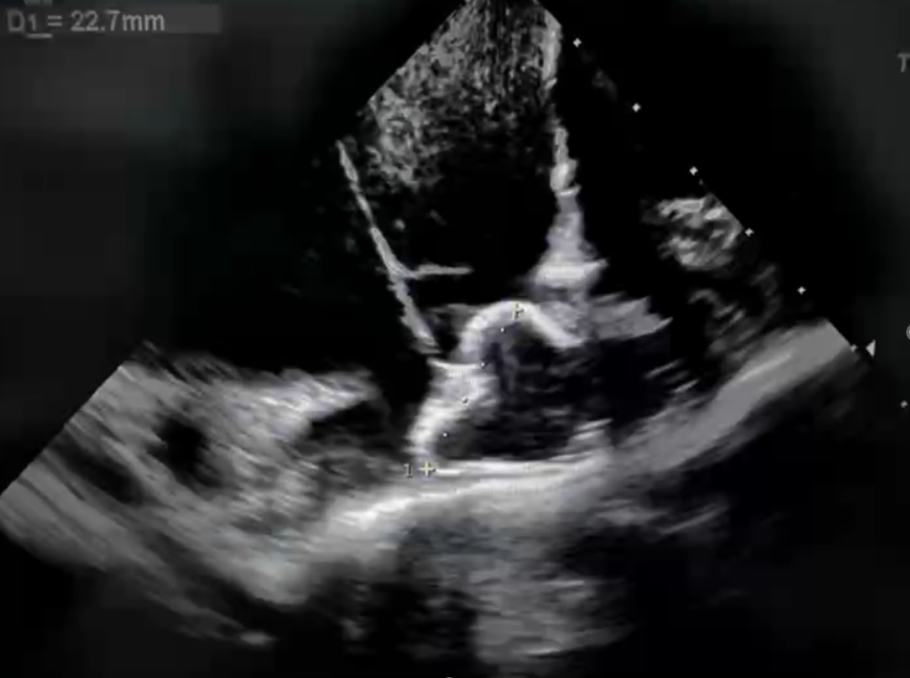

肝位下测量心耳开口、深度

术中ICE下测量心耳开口21.8mm,深度23.8mm,DSA下造影测量左心耳开口24mm,深度27mm,上下缘不对称,最终选择27mm的新一代封堵器进行封堵,一次展开即可达到一个非常好的封堵效果,封堵器与左心耳紧密贴合,形态、位置良好,无残余漏。